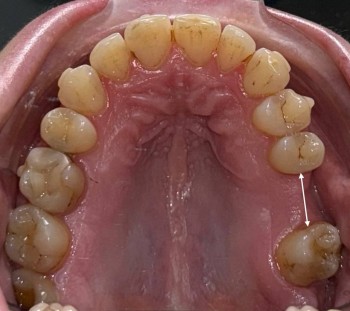

Примеры работ